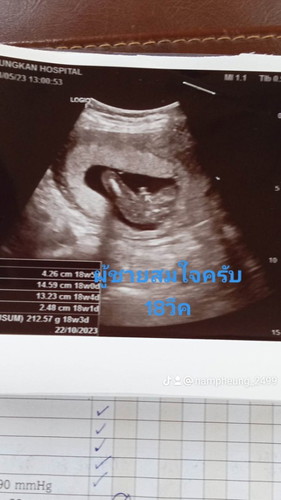

บ้านนี้รู้เพศตอน16วีค อัลตร้าซาวด์ที่คลินิค เมื่อวานนี้18วีค โรงพยาบาลนัดอัลตร้าซาวด์อีกที น้องอ้าขาโชว์จู๋มาเลยค่ะแม่ๆ 2ท้องแรกแม่ได้ลูกสาว ท้องนี้ท้องที่3 ได้ลูกชายสมใจจ้า พร้อมปิดอู่